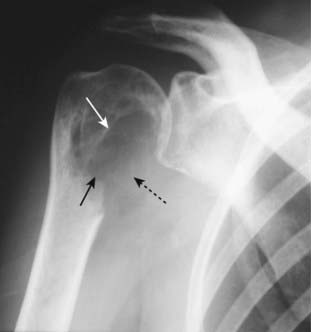

Figure 21-10 Avascular necrosis of humeral head.

There is increased density seen at the very top of the humeral head (solid black arrow) in this patient with sickle cell disease who developed avascular necrosis of the humeral head. Because the white cap on the bone looks like snow on a mountaintop, this sign of avascular necrosis has been called snow-capping.